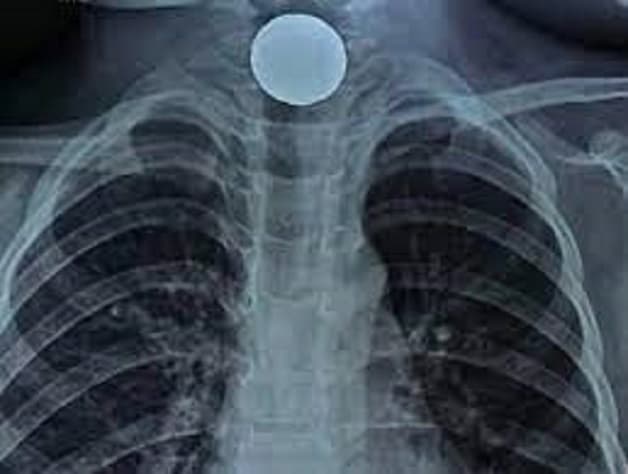

Dị vật khu vực thực quản là tai nạn nguy hiểm mà nhiều người có thể gặp phải (Ảnh minh họa)

Hóc dị vật thực quản có thể để lại nhiều biến chứng

Xử lý hóc dị vật thực quản kèm biến chứng thường không đơn giản